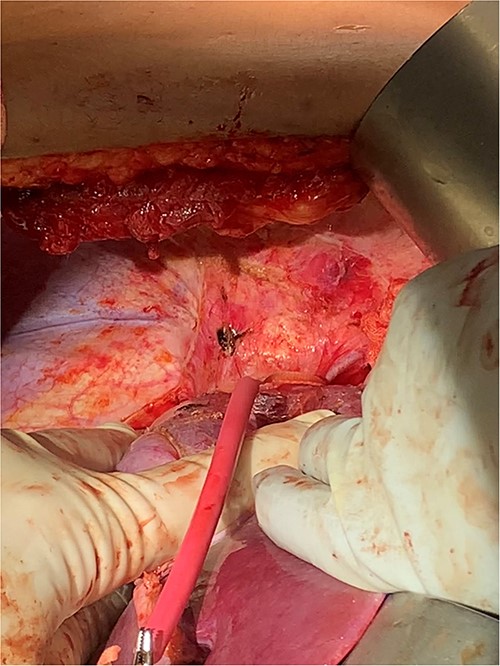

Detailed interdisciplinary coordination took place between Surgical Oncology, CTS, and Cardiac Anesthesia teams preoperatively. CT angiogram was repeated, which did not show thrombus past the mid-hepatic IVC. Given these findings, it was determined the thrombus should be removable with the tumor in the abdomen. However, CTS was maintained on standby should the need for bypass arise. An exploratory laparotomy was performed via a subcostal incision. Intraoperative ultrasound confirmed tumor thrombus did not extend superior to the hepatic vein takeoff. The suprahepatic vena cava was controlled with a Rummel tourniquet (Fig. 3). Ultrasound was again used and confirmed that all thrombus was below the level of the tourniquet.

The left renal rein and infrarenal IVC were dissected and controlled. At this point, the right kidney was mobilized for en-bloc resection, sparing the right adrenal gland. The ureter was ligated, and the right renal artery transected with a vascular stapler. Intraoperative ultrasound and transesophageal echocardiogram (TEE) were used to ensure that mobilization had not shifted the tumor thrombus. CTS was then called into the OR for confirmation. After heparin circulation, the suprahepatic IVC, left renal vein, and infra-hepatic IVC were occluded. The right renal vein was excised from the IVC at its origin, and the thrombus milked out in retrograde fashion (Fig. 4). The caval opening was controlled with a Satinsky clamp, while infrarenal and suprahepatic IVC clamps released. The cava was widely patent and the venotomy was repaired primarily. Completion intraoperative ultrasound and TEE were performed, all demonstrating satisfactory flow without residual tumor thrombus. The patient had an unremarkable recovery and was discharged on postoperative day 6 with therapeutic Lovenox and eventual transition to oral anticoagulation.